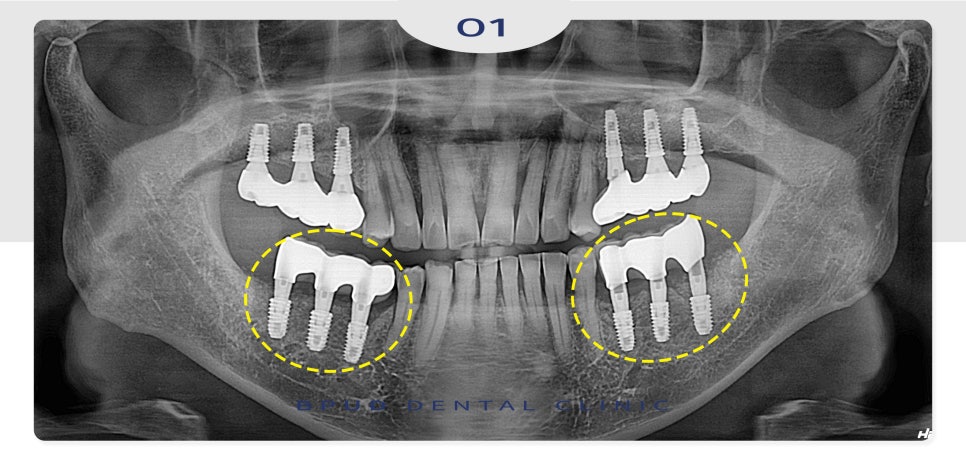

24.06.29

상악동 측방 거상법을 통해

넘어 가있는 임플란트를 제거한 후

염증 조직을 제거하고 가장 안쪽의 임플란트는

식립 없이 앞쪽 두 개의 보철만

재제작하여 장착해 드렸습니다.

추후 오른쪽 위 잇몸뼈의 소실이

관찰되는 임플란트도 상악동 내로

함입이 되기 전 제거해야 함을 설명드리고

제거 후 마찬가지로 앞쪽 두 개의 보철만

재제작하여 마무리하였습니다.